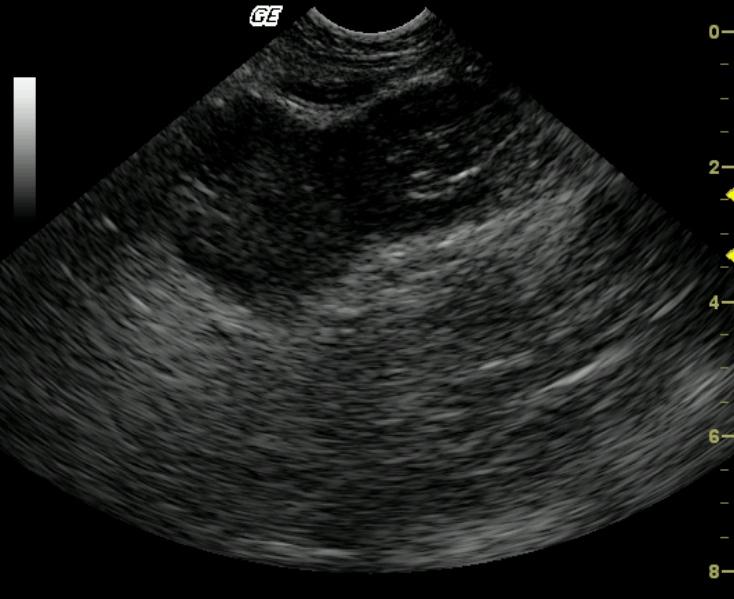

A hypoechoic, essentially bi-lobed small bowel wall mass is asymmetrically arising from a segment of distal small bowel. The serosal borders are undulating, however, the serosal layer appears to be intact.

Bolbedmasswithundulatingserosasmallbowelmass